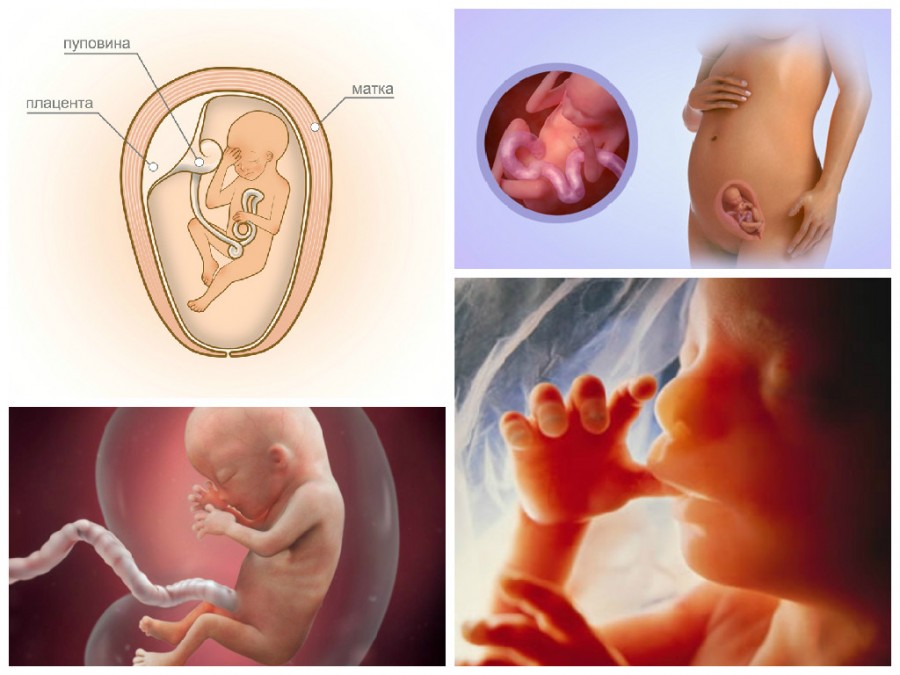

Развитие плода на восемнадцатой неделе беременности

Размер плода в среднем достигает 20 см, вес его равен 200-220 г. На данном этапе развития продолжает формирование нервная система ребенка. В первую очередь растет его головной мозг, на нем появляются первые борозды и извилины. У плода появляются нервы, по которым головной мозг посылает импульсы в различные системы его организма, формируется тимус – важная составляющая иммунной системы человека.

Известно, что на 18 неделе беременности плод активно реагирует на внешние световые раздражители. Он улавливает, где находится мама – в темноте или при ярком дневном свете. При этом глаза будущего ребенка находятся в закрытом состоянии. В целом его органы зрения полностью сформированы.

В этот период времени плод очень активен. Его тело еще легко помещается в матке, ему достаточно места для кувырканий и переворотов, способных доставить маме много новых ощущений.

Какие параметры фиксируются во время УЗИ

- окружность головы и живота;

- длина бедренной и плечевой кости;

- предполагаемая масса плода;

- примерный объем околоплодных вод;

- положение плаценты (прикрепление к передней или задней стенке);

- прикрепление пуповины, количество сосудов и кровоток в них;

- сердцебиение плода;

- длина шейки матки.

Эти данные помогают оценить скорость развития плода в соответствии со сроками беременности, выявить генетические патологии, риски угрозы прерывания.